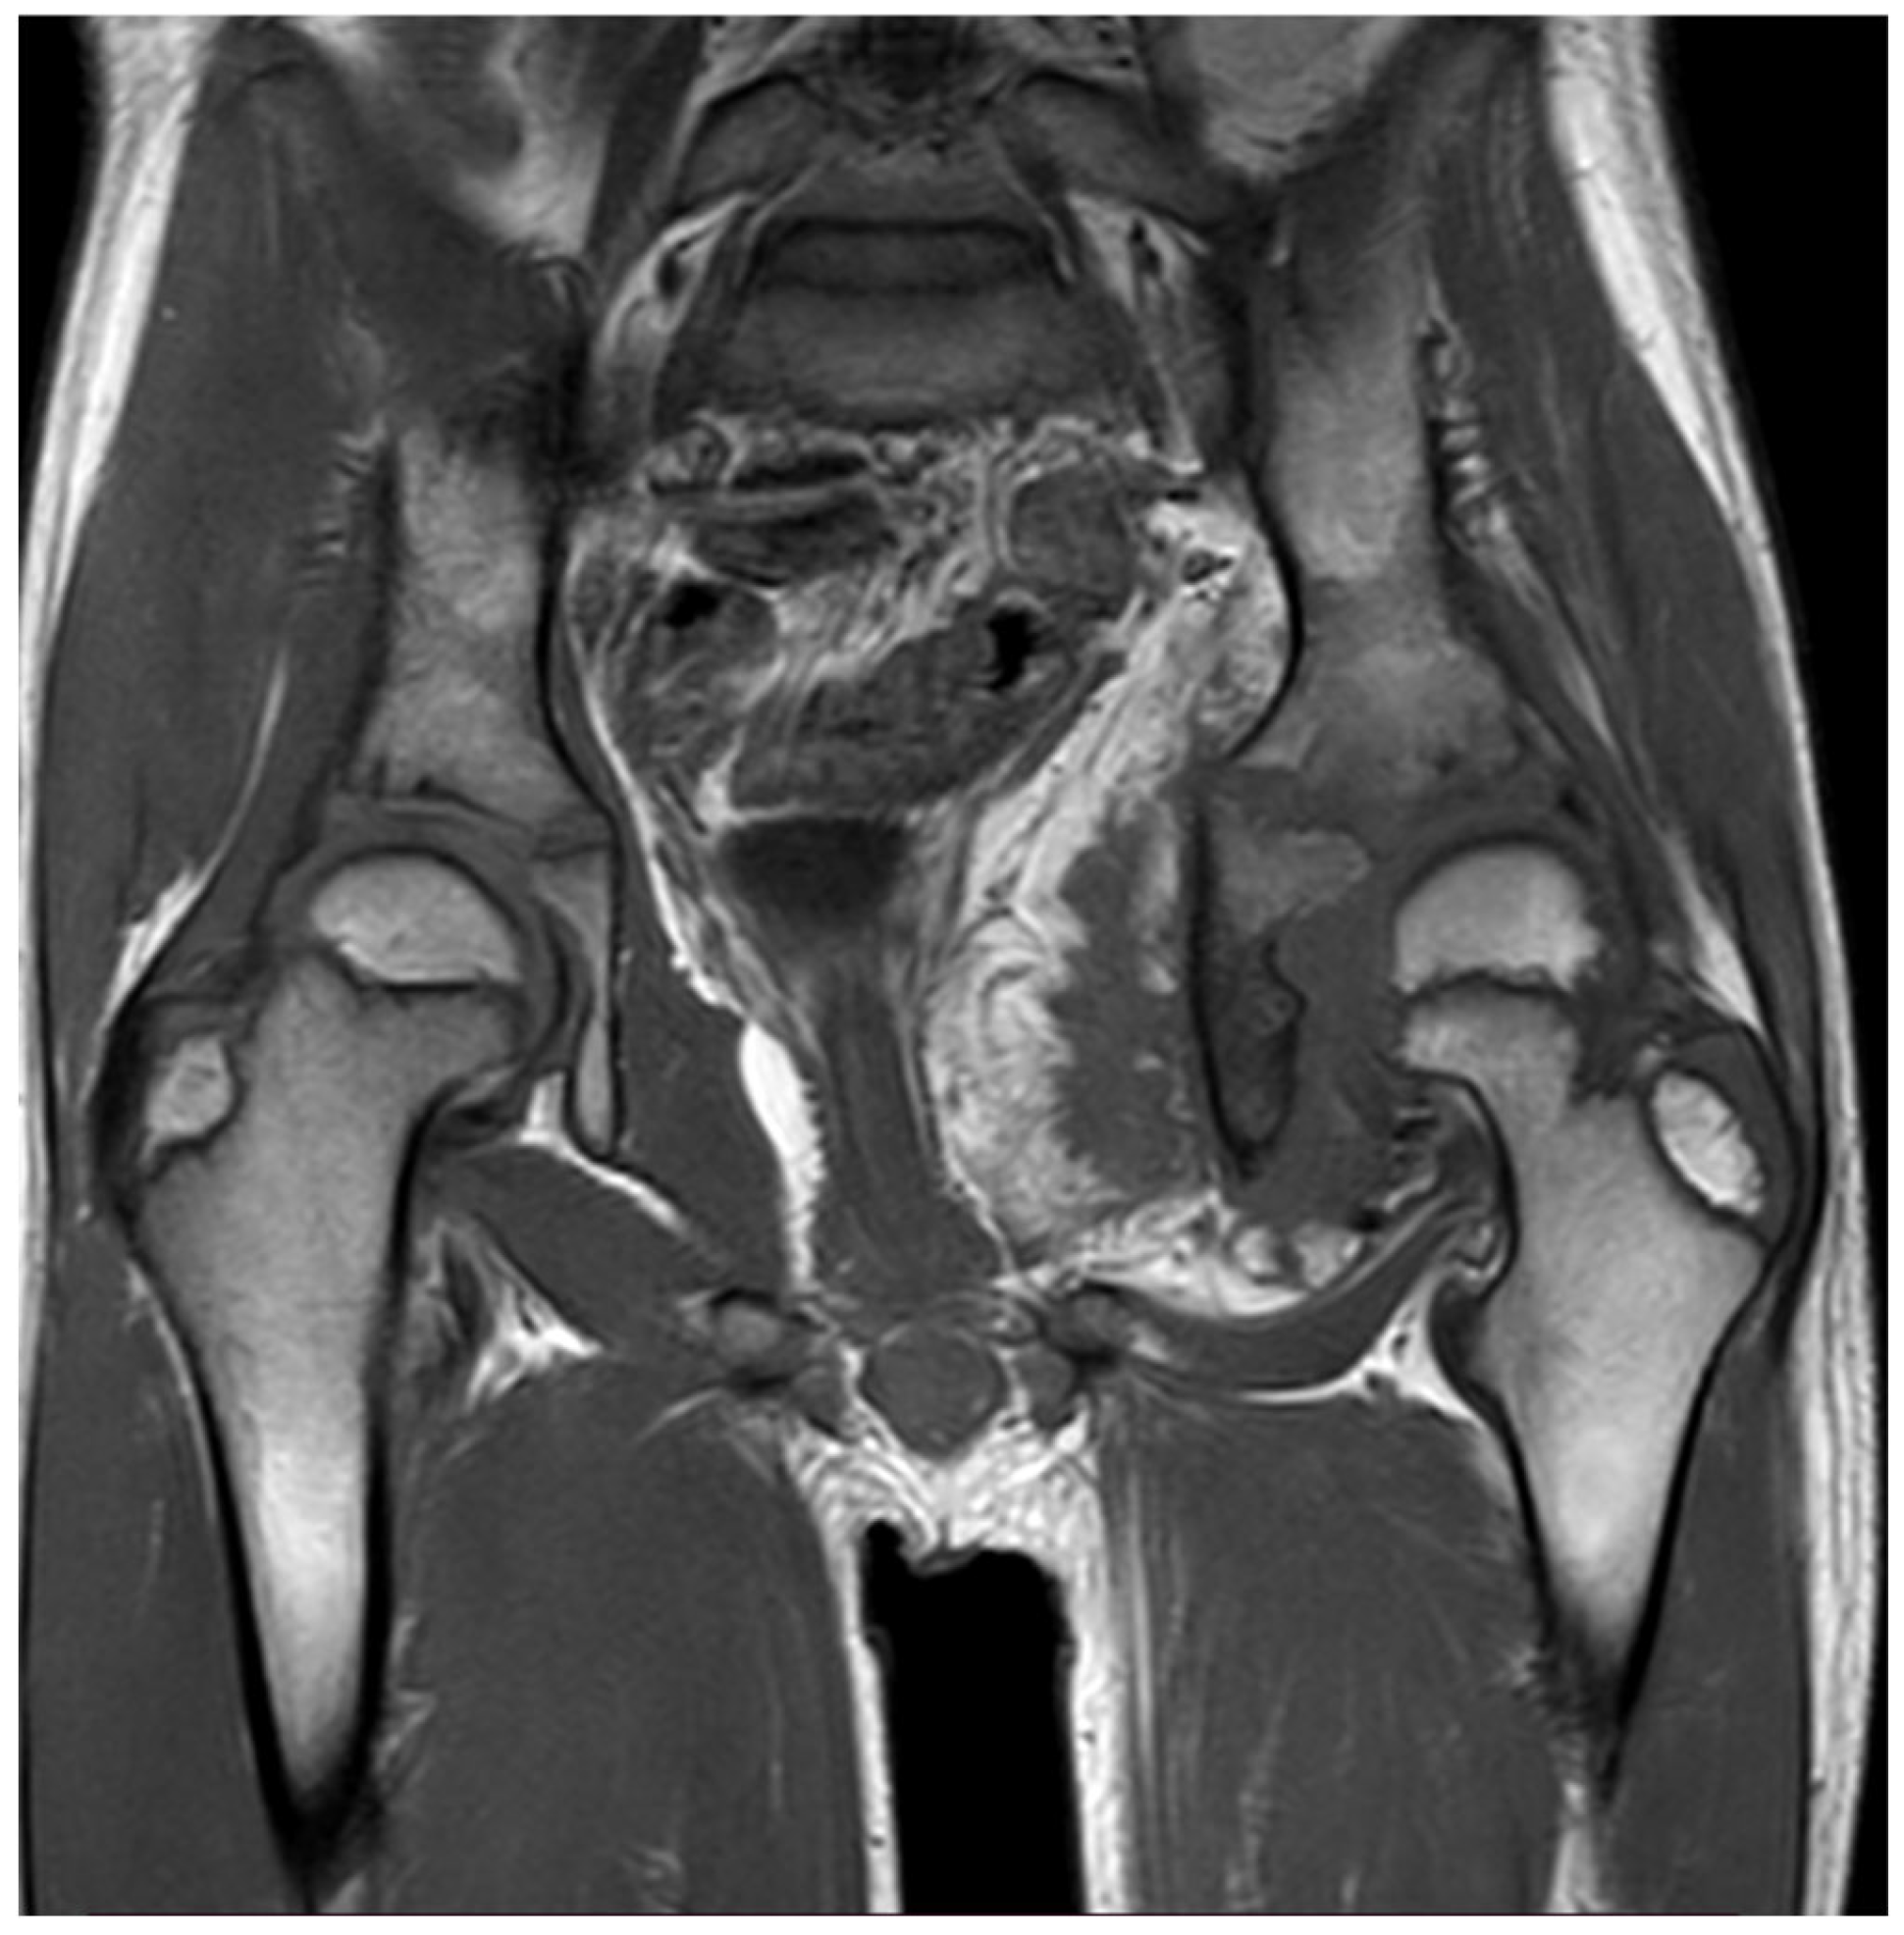

Thirteen months later, the patient underwent a new pelvis MRI examination due to the worsening of symptoms and a significant decrease in range of motion of the left hip. MRI revealed a large heterogeneous soft-tissue mass in the abdominal cavity, with extension to the hip joint, presenting both fat and muscle signal intensity with heterogeneous enhancement post gadolinium, and associated with extensive peri-osseous fatty infiltration, a reactive soft-tissue component, and advanced severe atrophy of the left obturator muscles (Figure 1). Those findings were not observed in the previous MRI.

Imaging is considered the gold standard for the diagnosis of myolipoma. Ultrasound may suggest the presence of a myolipoma, as the lipomatous regions of the tumor appear hyperechogenic; however, it cannot provide a definitive diagnosis. On CT and MRI, the lipomatous areas demonstrate typical fat characteristics. In contrast, the non-lipomatous regions display nonspecific solid features, with soft-tissue attenuation on CT, intermediate signal intensity on T1-weighted MRI, and intermediate to high signal intensity on T2-weighted MRI. [5]. The MRI we’ve done to our patient showed extensive peri-osseus fatty infiltration by soft tissue reaction which correlates with the fact that MRI shows the features of fat tissue in lipomatous components of myolipoma.

Figure 1. MRI showing large heterogeneous soft-tissue mass in the abdominal cavity, with extension to the hip joint.